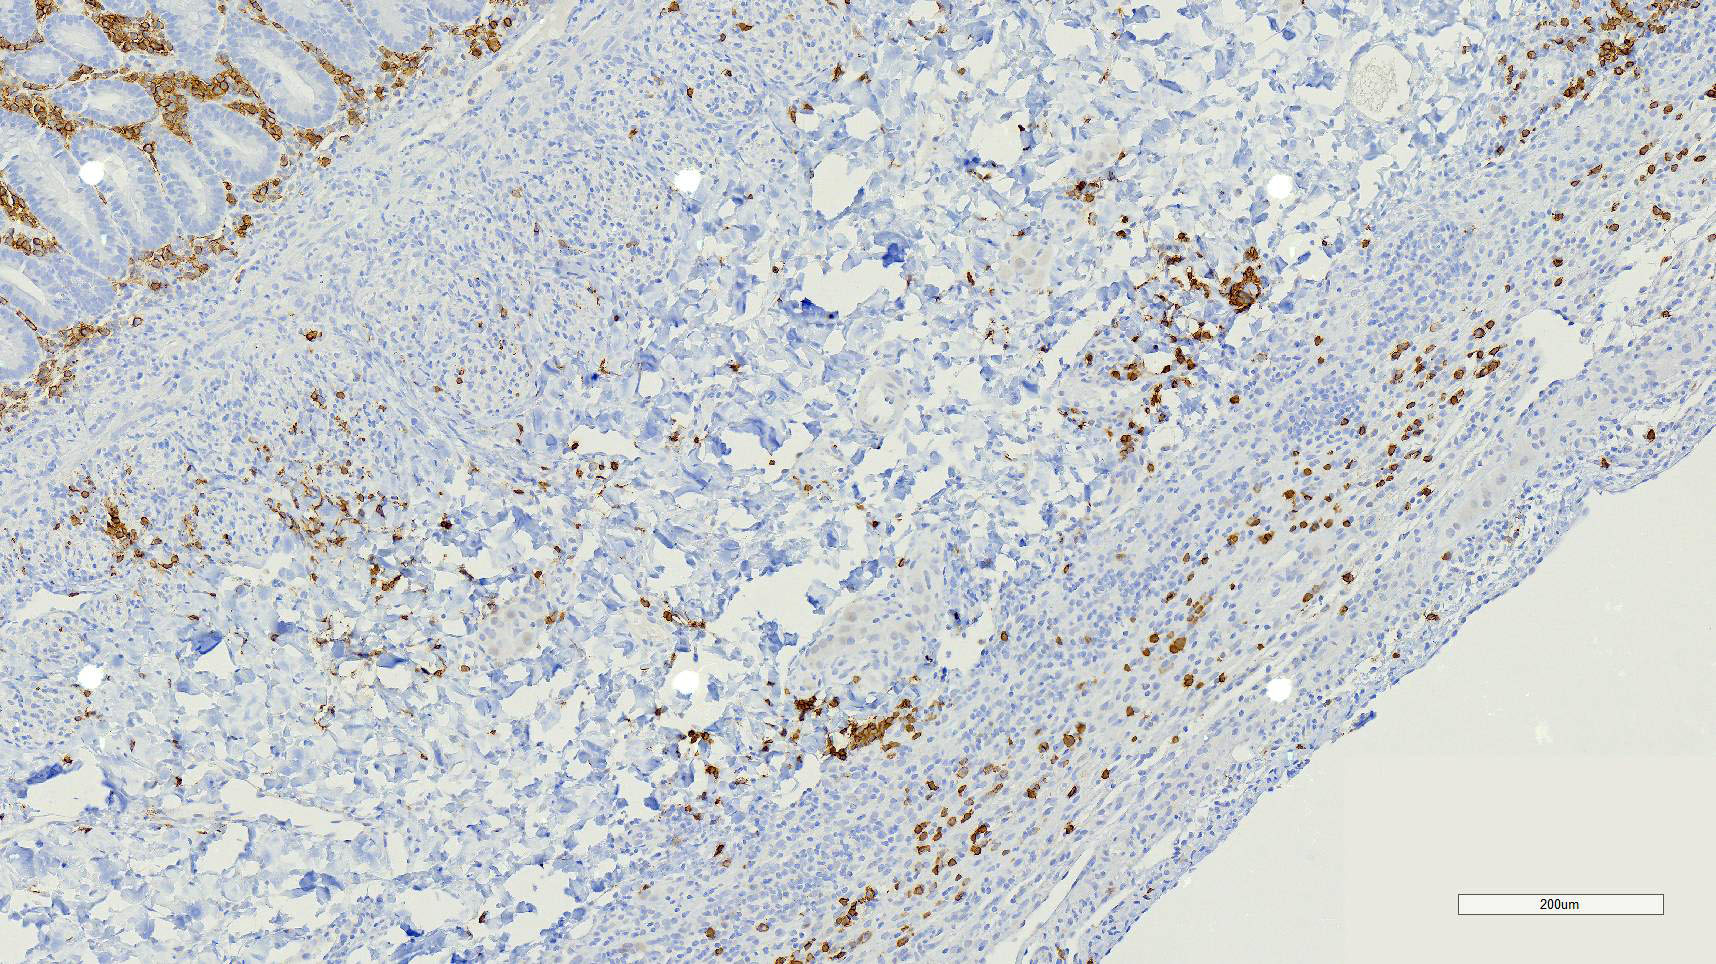

Duodenum, jejunum and ileum: Diffusely throughout the sections, there is partial to complete loss of the leiomyocytes of the outer and inner muscularis, which are multifocally replaced by loose fibrous connective tissue (fibrosis). The remaining smooth muscle is infiltrated by large numbers small and intermediate lymphocytes, few macrophages and neutrophils. The same inflammatory infiltrate is present throughout the muscularis mucosae. Remaining leiomyocytes have pale, frequently vacuolated cytoplasm. In the submucosa, muscularis and serosa there are small to moderate numbers of perivascular lymphocytes. Small lymphocytes, and infrequently neutrophils, surround or infiltrate the myenteric and submucosal ganglia, though neurons do not exhibit degenerative changes. The lamina propria contains a markedly increased number of lymphocytes, plasma cells and a mildly increased number of eosinophils. The epithelium is diffusely overlain by myriad bacterial rods. The serosa is mildly expanded by increased clear space (edema) and is lined multifocally by markedly hypertophied mesothelium. In the stomach a similar process is observed but restricted to the outer aspect of the muscularis with a patchy/multifocal distribution and sparing of the muscularis mucosae. (section not submitted).

Duodenum, jejunum and ileum: Severe, diffuse, chronic lymphocytic leiomyositis with severe muscularis atrophy; marked, diffuse, chronic lymphoplasmacytic enteritis.

Microscopic findings reported for this condition consist of mild to marked mononuclear infiltrate, myofiber degeneration and fibroplasia or fibrosis centered within the muscularis propria of the stomach, small and large intestinal wall with the jejunum being the most severely and chronically affected segment.7,15 In early lesions the inflammation and smooth muscle degeneration are segmental, random between the outer and inner muscularis layers and sparing of the muscularis mucosae.15 Concurrent cecal involvement leading to impaction has also been described.5 Consistent histologic findings included T-lymphocyte inflammation within the muscularis propria with relative sparing of the mucosa, submucosa and neural plexuses.14 In one case report the inflammatory infiltrate was predominantly of B-lymphocytes and featured extensive angiogenesis.6 Leiomyocytes appear to be the target of the inflammation given the presence of various stages of degeneration leading to complete myofiber loss in chronic stages of the disease. Superficial inflammation is a frequent secondary finding in CIPO and has been associated with bacterial overgrowth, which were changes observed in this case.6 Neuropathy has not been a feature in most reports of canine CIPO. Inflammatory cells obscuring the myenteric and submucosal plexuses in this case were considered an extension from the neighboring inflammation as no degenerative changes were observed in the neurons. Myenteric ganglionitis has, however, been reported occurring concurrently with leiomyositis.10

Small intestine: Leiomyositis, lymphocytic, chronic, diffuse, severe, with marked smooth muscle loss and fibrosis.